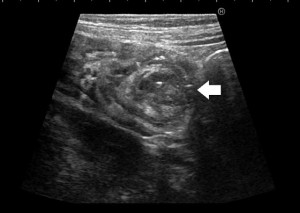

<Abstract:> Infection with Yersinia pseudotuberculosis, a known causal pathogen of human bacterial gastroenteritis, causes various symptoms and complications. A previously healthy 7-year-old girl was admitted because of fever and gastrointestinal symptoms. She was initially diagnosed with intussusception by abdominal ultrasonography. Although the patient was successfully treated by air enema, the fever persisted. The patient was then diagnosed with incomplete Kawasaki disease based on the presence of four principal clinical features. Intravenous immunoglobulin and oral aspirin were initiated. The patient defervesced and the other symptoms subsided after the treatment. Cardiac ultrasound results showed normal coronary arteries. Because of the gastrointestinal symptoms, stool samples were cultured repeatedly, only to yield normal flora. However, serum levels of anti-Y. pseudotuberculosis-derived mitogen antibody were elevated between the 7th and 18th days of the disease, thereby confirming Y. pseudotuberculosis infection. Because Y. pseudotuberculosis infection results in various clinical manifestations, we must be aware of each symptom and address them systematically.